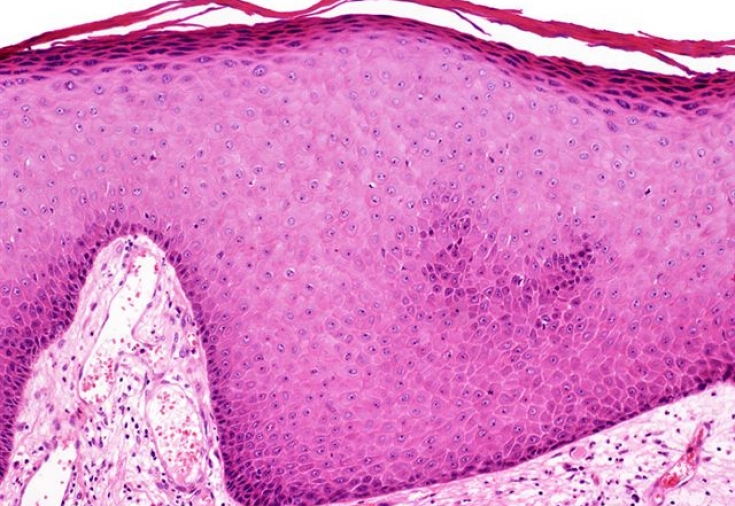

- Гіперкератоз, який провокує огрубіння та відлущування шкіри.

На ранніх етапах розвитку акантозу шкіра хворого поступово темніє. Багато хто намагається шкіру ретельно мити, думаючи, що вона брудна. У міру прогресування хвороби шкіра починає ще більше темніти, стає шорсткою, сухою, потовщується. Природний малюнок шкіри стає більш вираженим та глибоким.

На пізніших стадіях на уражених ділянках шкіри з'являються розростання у вигляді фібром та дрібних папілом. Розростання мають сосочкоподібну форму і розташовуються щільними рядами, надаючи шкірі бородавчастого вигляду. Ці утворення також можуть бути гіперпігментовані. Всі симптоми акантозу на шкірі супроводжуються легким свербінням і поколюванням. Волосяний покрив на уражених ділянках шкіри відсутній.

При виявленні потемніння шкіри на окремих ділянках шкіри, яке не проходить, а лише прогресує, варто звернутися до дерматолога. Фахівець проведе диференціальну діагностику із хворобою Аддісона, іхтіозом, хворобою Дар'ї. Заключний діагноз чорного акантозу встановлюється на підставі дослідження гістологічного біоптату. При підозрі на злоякісну форму потрібна консультація онколога.